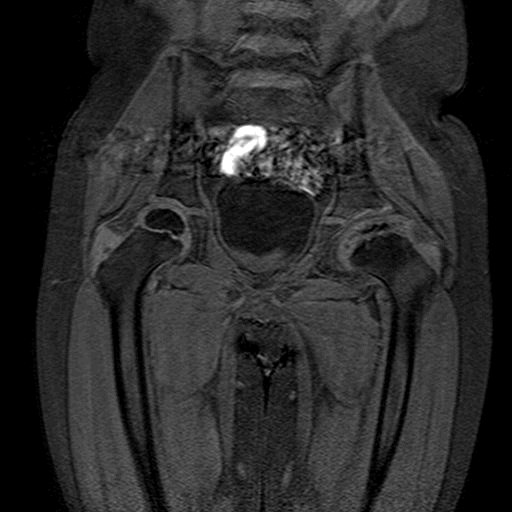

Illustration 13 : Séquence T1. Fragmentation et coxa plana à gauche. Notez le cartilage qui apparaît en gris clair autour des têtes fémorales et du cotyle. (source : hôpital Robert Debré).

Illustration 14 : Séquence T2. On note une fracture sous-chondrale et une excentration de la tête fémorale gauche. L'épanchement apparaît en blanc entre le cotyle et la tête.(source : hôpital Robert Debré)

Illustration 13 : Séquence T1. Fragmentation et coxa plana à gauche

Illustration 14 : Séquence T2. Fracture sous-chondrale et excentration de la tête fémorale gauche